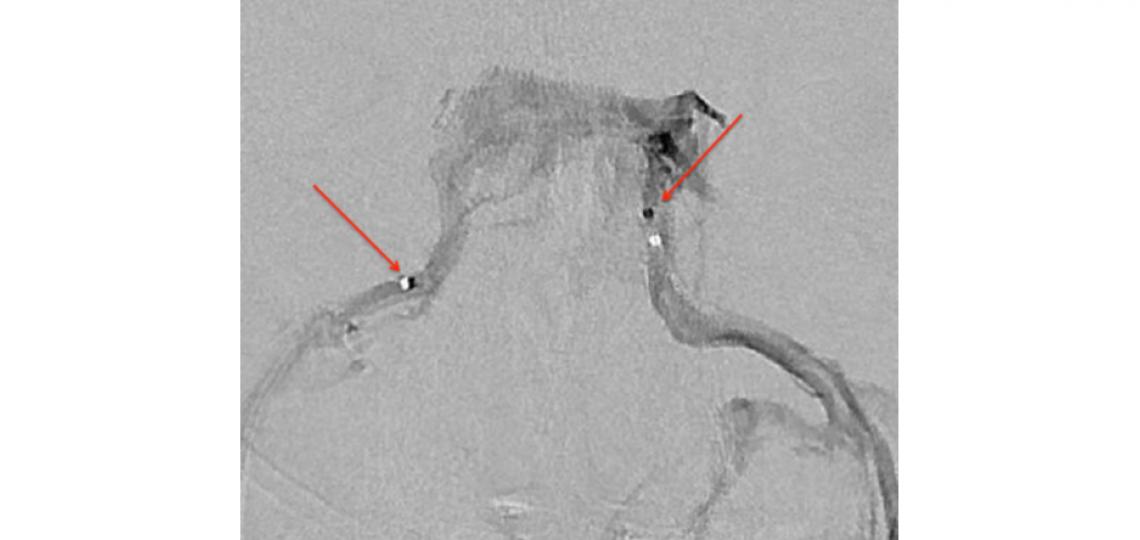

Cerebral venogram outlining bilateral cavernous sinuses and inferior petrosal sinuses. A microcatheter (arrow) is seen in each inferior petrosal sinus.